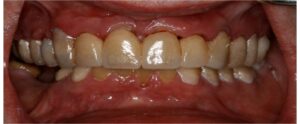

Η Προσθετικη οδοντιατρικη ειναι ο κλαδος της οδοντιατρικης που ασχολειται με την αποκατασταση μεγαλης η μικρης νωδοτητας στον οδοντικο φραγμο.

Η Προσθετικη Οδοντιατρικη χωριζεται σε

- Ακινητη προσθετικη, δηλαδη στεφανες και γεφυρες

- Κινητη προσθετικη, δηλαδη μερικες και ολικες οδοντοστοιχιες

- Προσθετικη επι εμφυτευματων